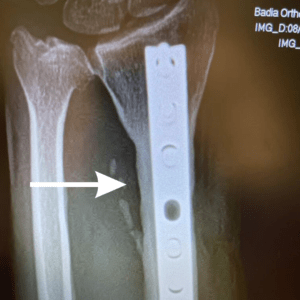

After X-Rays shows bone remodeling after 28 years. Graft was taken from iliac crest ( Pelvis).